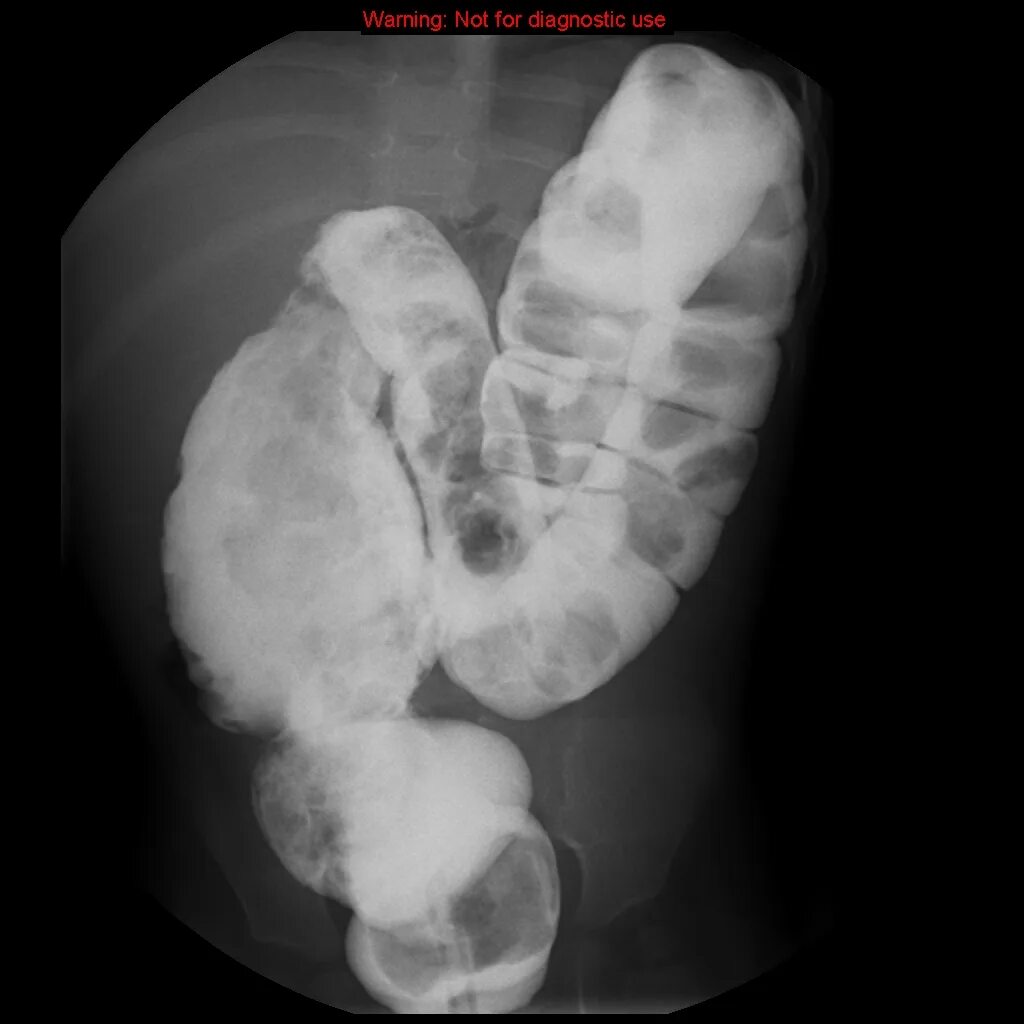

Идиопатический мегаколон по утвержденным клиническим рекомендациям 2025